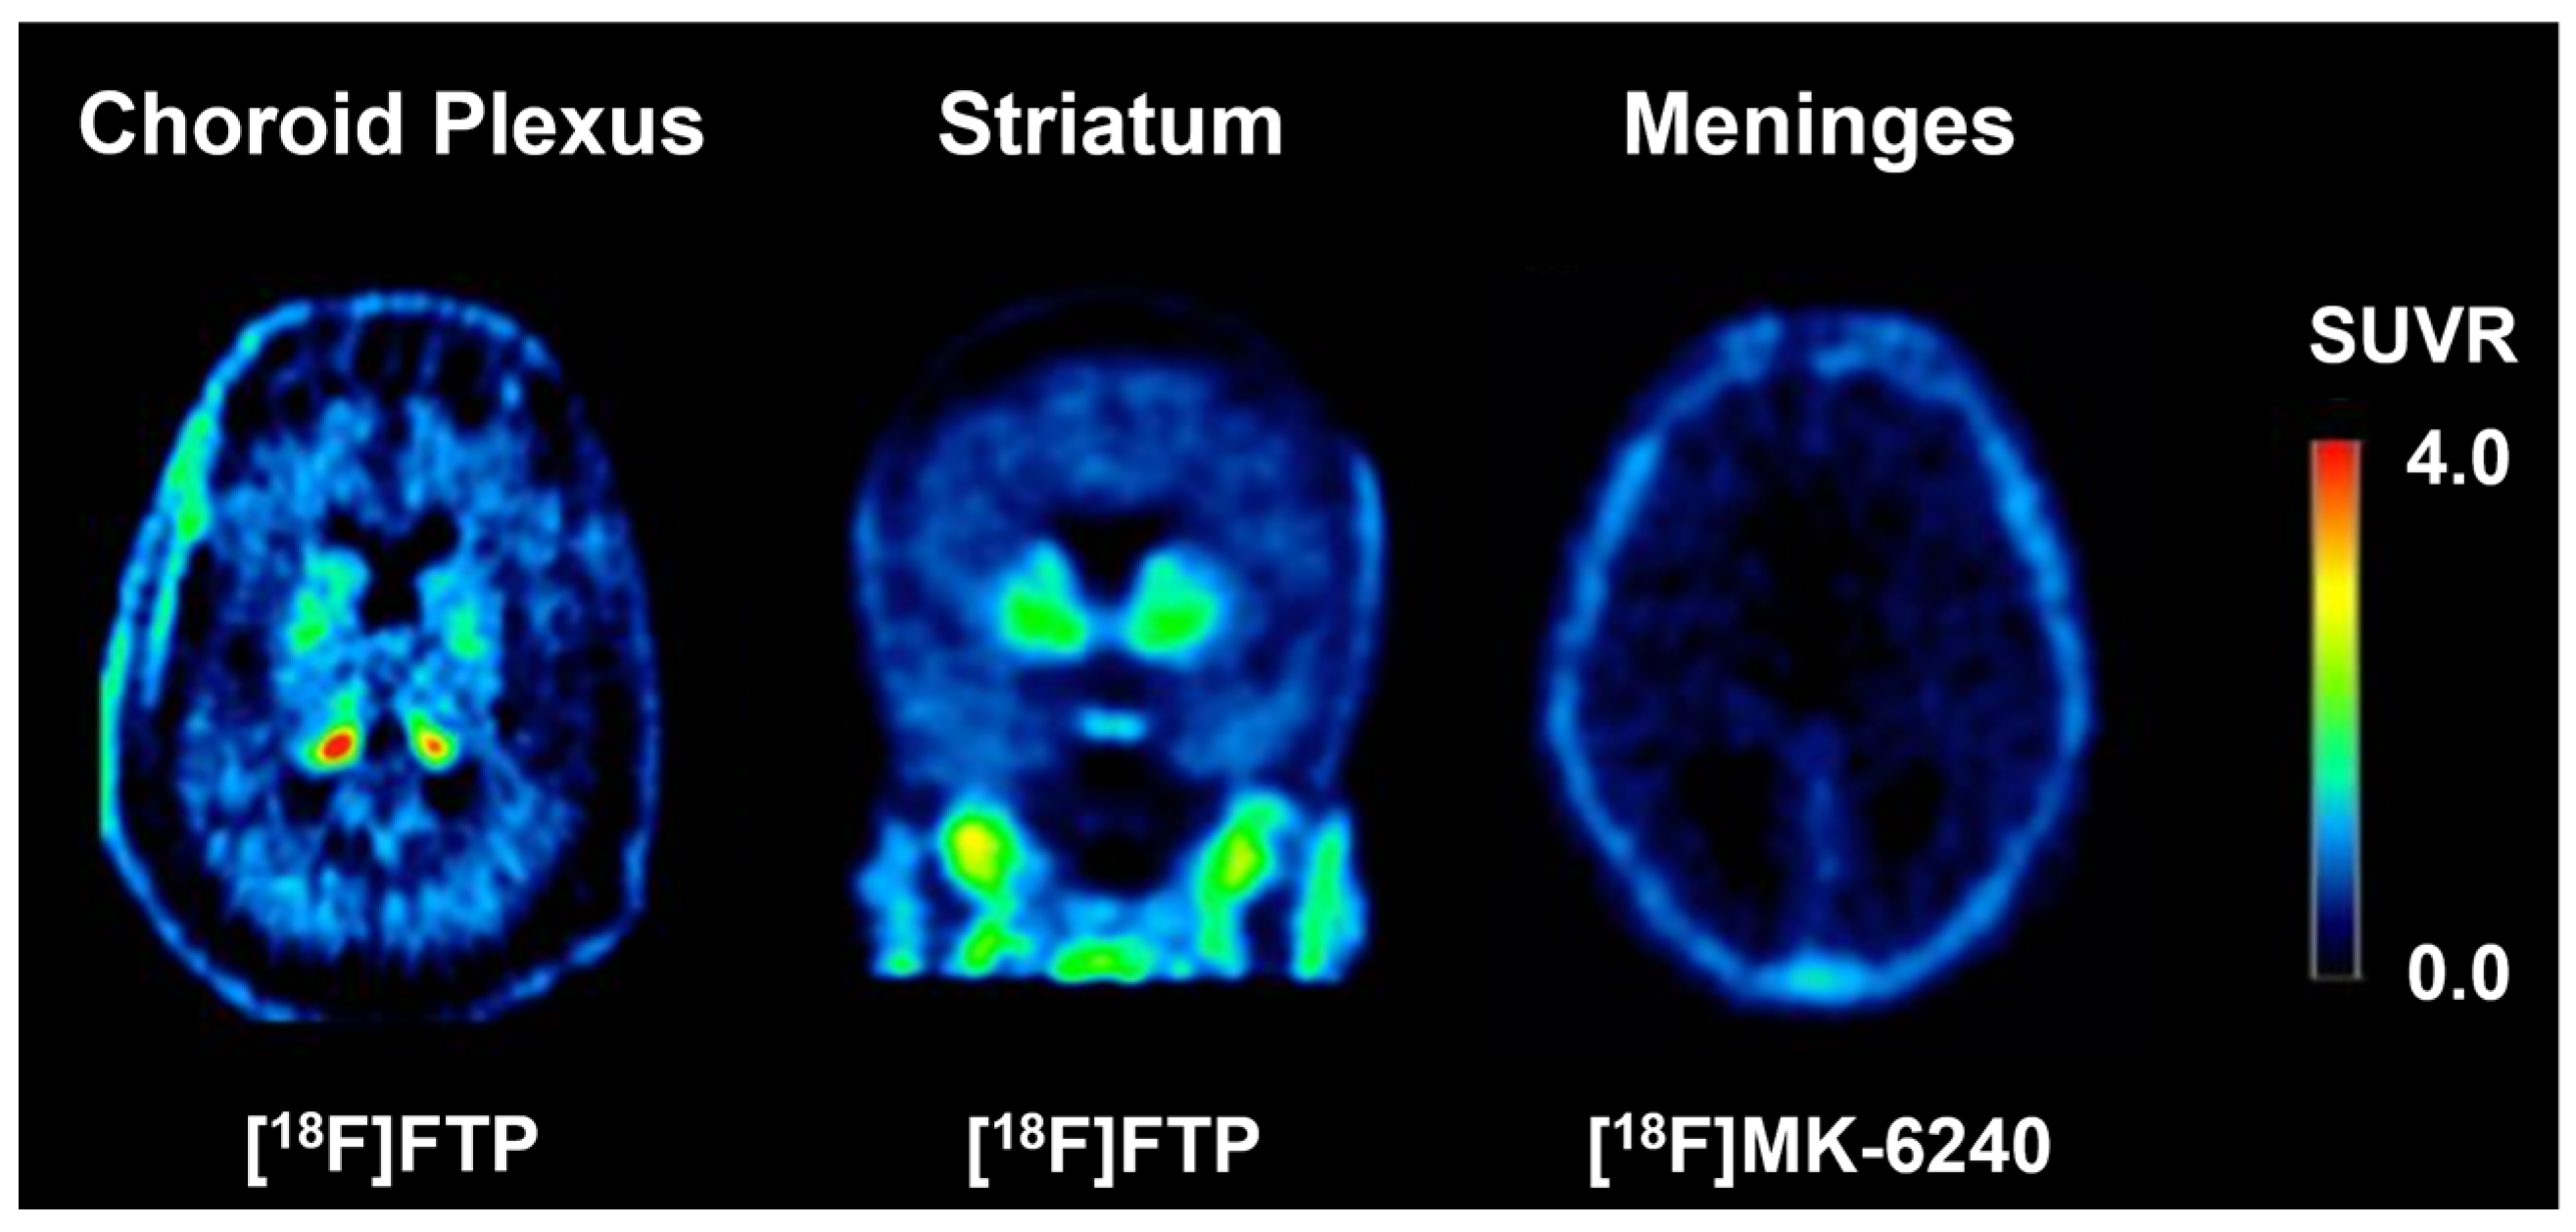

- Choi, J.Y.; Cho, H.; Ahn, S.J.; Lee, J.H.; Ryu, Y.H.; Lee, M.S.; Lyoo, C.H. Off-Target (18)F-AV-1451 Binding in the Basal Ganglia Correlates with Age-Related Iron Accumulation. J. Nucl. Med. 2018, 59, 117–120. [Google Scholar] [CrossRef]

- Lee, C.M.; Jacobs, H.I.L.; Marquié, M.; Becker, J.A.; Andrea, N.V.; Jin, D.S.; Schultz, A.P.; Frosch, M.P.; Gómez-Isla, T.; Sperling, R.A.; et al. 18F-Flortaucipir Binding in Choroid Plexus: Related to Race and Hippocampus Signal. J. Alzheimer’s Dis. 2018, 62, 1691–1702. [Google Scholar] [CrossRef]

- Lowe, V.J.; Curran, G.; Fang, P.; Liesinger, A.M.; Josephs, K.A.; Parisi, J.E.; Kantarci, K.; Boeve, B.F.; Pandey, M.K.; Bruinsma, T.; et al. An autoradiographic evaluation of AV-1451 Tau PET in dementia. Acta Neuropathol. Commun. 2016, 4, 58. [Google Scholar] [CrossRef] [PubMed]

- Aguero, C.; Dhaynaut, M.; Normandin, M.D.; Amaral, A.C.; Guehl, N.J.; Neelamegam, R.; Marquie, M.; Johnson, K.A.; El Fakhri, G.; Frosch, M.P.; et al. Autoradiography validation of novel tau PET tracer [F-18]-MK-6240 on human postmortem brain tissue. Acta Neuropathol. Commun. 2019, 7, 37. [Google Scholar] [CrossRef] [PubMed]

- Smith, R.; Strandberg, O.; Leuzy, A.; Betthauser, T.J.; Johnson, S.C.; Pereira, J.B.; Hansson, O. Sex differences in off-target binding using tau positron emission tomography. Neuroimage Clin. 2021, 31, 102708. [Google Scholar] [CrossRef] [PubMed]

- Villemagne, V.L.; Lopresti, B.J.; Doré, V.; Minhas, D.; Gogola, A.; Nadkarni, N.; Mason, N.S.; Bourgeat, P.; Lopez, O.; Ikonomovic, M.D.; et al. Traits and Trammels of Tau Tracer Imaging. In Molecular Imaging of Neurodegenerative Disorders; Cross, D.J., Mosci, K., Minoshima, S., Eds.; Springer International Publishing: Cham, Switzerland, 2023; pp. 85–107. [Google Scholar]